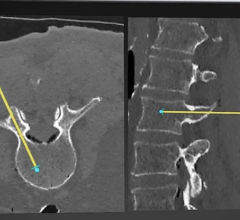

May 30, 2024 — Vuze Medical, which develops medical technology to transform intra-operative guidance in spinal ...

May 29, 2024 — The Radiological Society of North America (RSNA) has launched the 2024 RSNA Lumbar Spine Degenerative ...